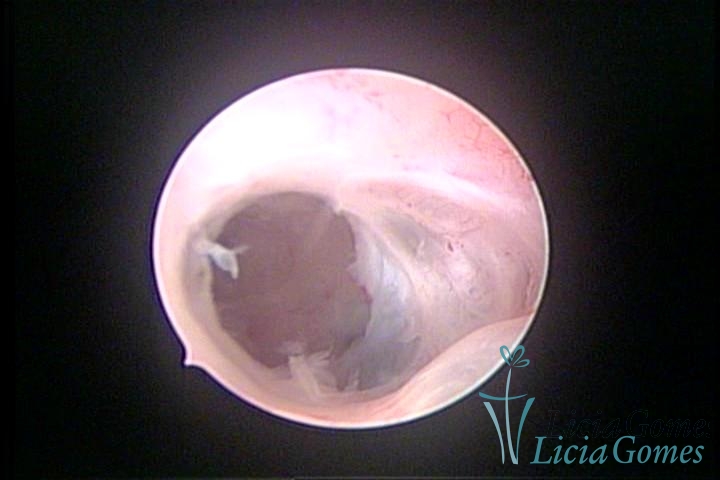

• SINÉQUIA TIPO FIBROMUSCULAR